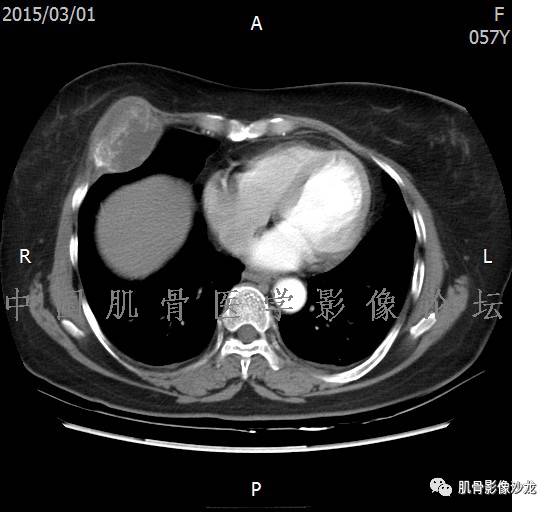

雪舞 :第二例,位于骶骨,有骨质破坏并有软组织肿块,软组织肿块边界清

雪舞: 第二例我们能够看到破坏与软组织肿块不成比例,软组织肿块大,破坏小

雪舞 :第二例挺难的,骨质破坏是溶骨性的,局部皮质中断,软组织肿块外缘光滑

雪舞 : 软骨肉瘤的发病率居原发性恶性骨肿瘤的第三位,其特点是肿瘤内具有软骨基质

雪舞:弓形钙化,钙化比例少于面积的1/3,钙化边缘模糊

雪舞 : 都是软骨肉瘤鉴别于内生软骨瘤有意义的区别点